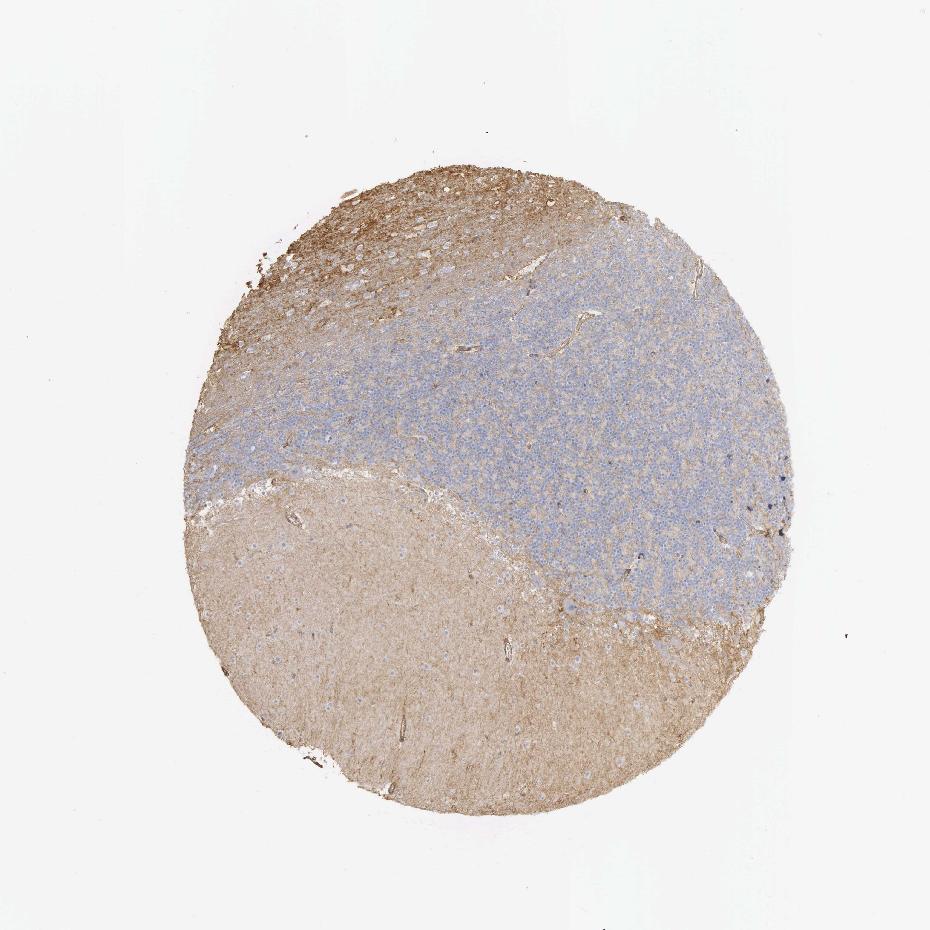

CEREBELLUM - Antibody stainingi

Antibody staining in the annotated cell types in the current human tissue is reported as not detected, low, medium, or high, based on conventional immunohistochemistry profiling in selected tissues. This score is based on the combination of the staining intensity and fraction of stained cells.

Each image is clickable and will lead to virtual microscopy that enables deeper exploration of all samples and also displays staining intensity scores, fraction scores and subcellular localization as well as patient and tissue information for each sample.

Antibody HPA035304Antibody CAB000020

Molecular layer - neuropil -Medium

Processes in granular layer -Low

Processes in molecular layer -Medium

Processes in white matter -High

Synaptic glomeruli - capsule -Low

Synaptic glomeruli - core -Not detected

White matter cells - cytoplasm/membrane -Medium

White matter cells - nucleus -Not detected